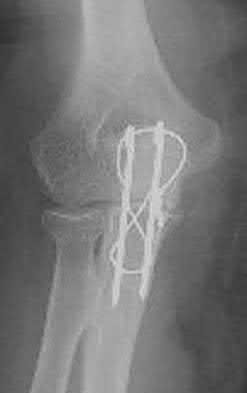

A 51-year-old carpenter presents with a distal humerus nonunion (Figures A and B). After repair of the nonunion, he is lost to follow up for 3 months and then presents to your clinic pain-free and with evidence of fracture union. On examination the elbow arc of motion is 10-80 degrees. Following a brief failed trial of conservative management, you recommend:

Limited flexion outside a functional range of motion (30-130 degrees) can be quite debilitating, and it is often addressed with open release of the posterior bundle of the MCL and posterior capsule and excision of osteophytes.

A frequent complication of distal humerus fractures is post-traumatic stiffness. This patient has had multiple procedures about the distal humerus, and the question stem implies that he did not complete a structured range of motion protocol following the repair of his nonunion. Beyond a trial of conservative management, there are many techniques described for capsule and soft tissue releases as well as bony resections if heterotopic ossification is present. This patient's severely limited flexion would best be addressed with a release of the posterior bundle of the MCL, and with flexion